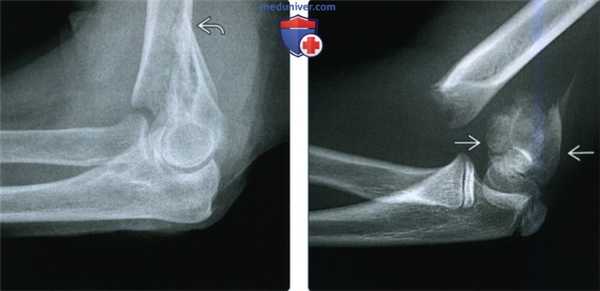

(Слева) В боковой проекции у женщины 87 лет после падения определяется повреждение Гартланда II типа с задним смещением мыщелков плечевой кости относительно диафиза и задним угловым отклонением, но с сохранением контакта с задним кортикальным слоем.

(Справа) На снимке в боковой проекции у девятилетнего ребенка определяется полное смещение кзади мыщелков плечевой кости и отсутствие контакта между отломками, составляющими повреждение Гартланда III типа. Поскольку перелом не переходит на мыщелки, он является истинным надмыщелковым переломом.